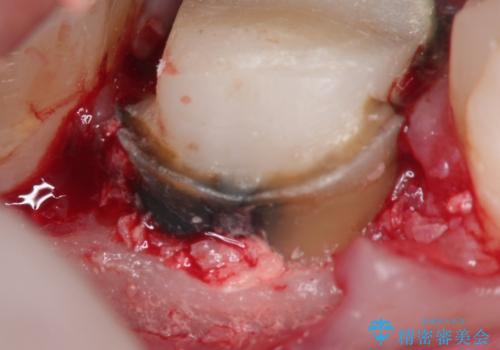

- 奥歯がズーンと痛いことを主訴に来院されました。

根管治療時に穿孔部位を認め、MTAにて修復し、分岐部の歯周ポケットおよび骨欠損に対しては、再生治療を行うことで、正常な歯周状態の獲得ができました。